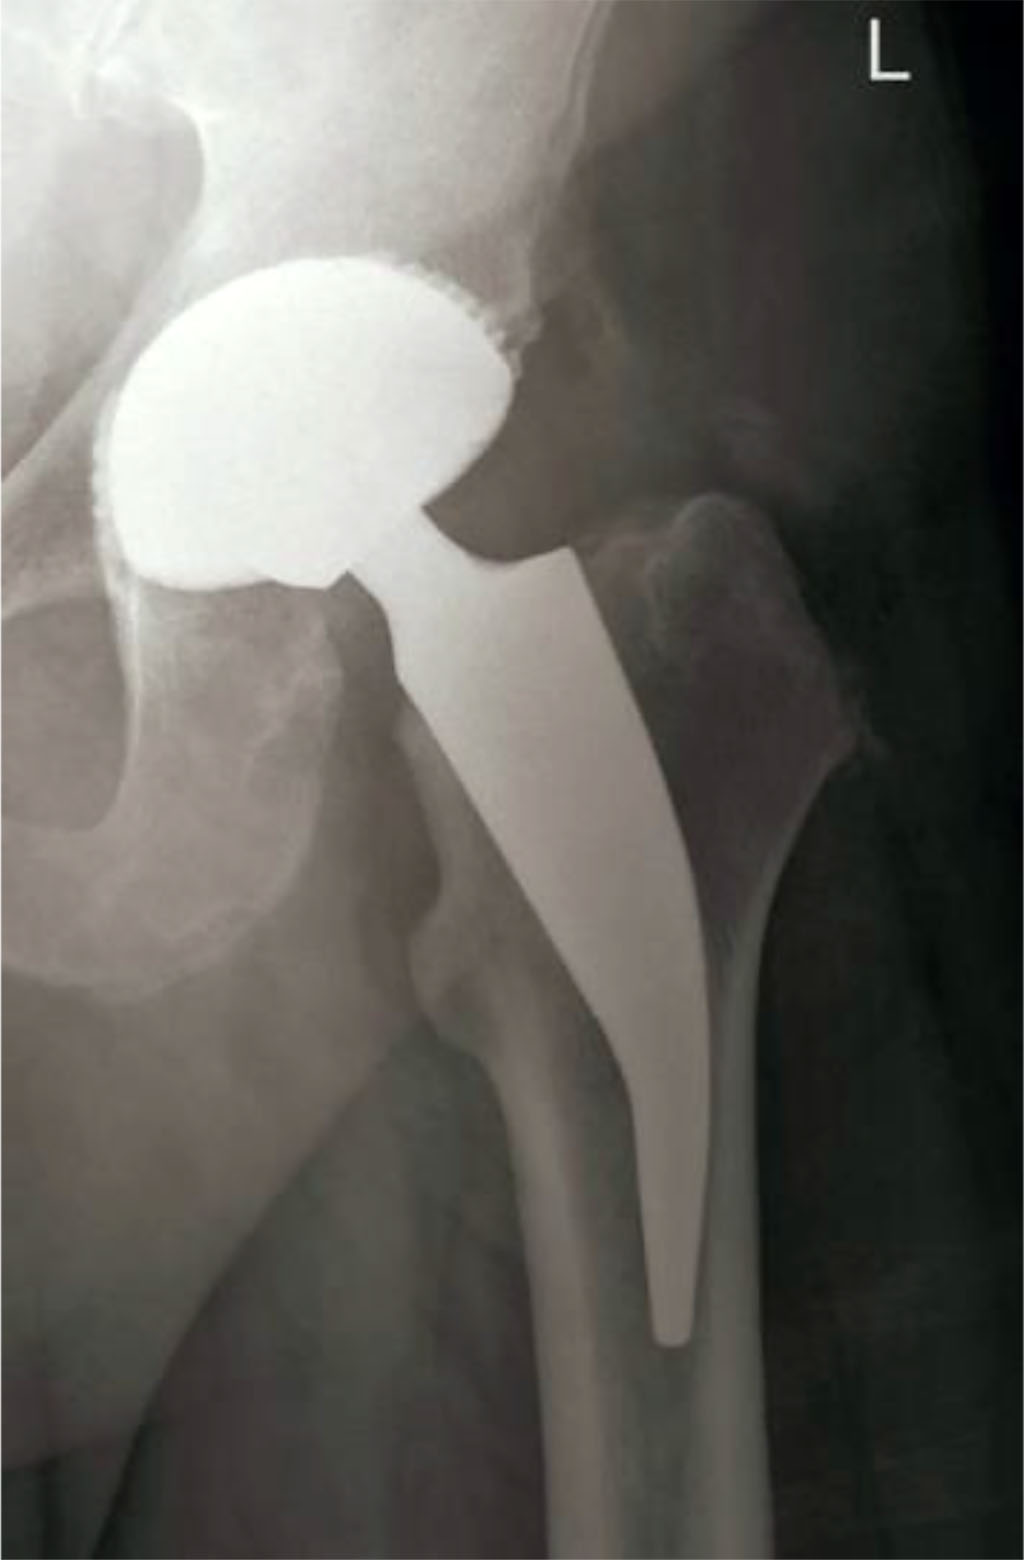

Fig 1. Radiological examination of the left hip joint after the surgery – THA [44].